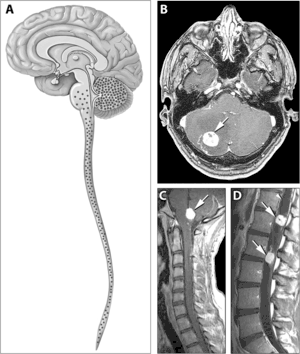

希佩尔-林道综合征(Von Hippel–Lindau disease,VHL综合征)是一种罕见的常染色体显性遗传性疾病[1],表现为血管母细胞瘤累及小脑、脊髓、肾脏以及视网膜。其若干病变包括肾脏血管瘤、肾细胞癌以及嗜铬细胞瘤等。疾病是因位于染色体3P25.3的VHL抑癌基因发生突变所致。[2]

VHL的临床表现和症状包括血管瘤、血管母细胞瘤、嗜铬细胞瘤、肾细胞癌,胰腺囊肿(胰腺浆液性囊腺瘤)以及咖啡牛奶斑[3]。37.2%的VHL患者表现为血管瘤,且通常累及视网膜,由此产生的失明十分常见。其他脏器也会受累,由此带来的中风、心脏病、心血管疾病也相当多见。[2]